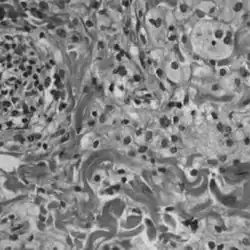

Histopathology slide of Erdheim-Chester disease

A definitive diagnosis of ECD is made when CD68-positive, CD1a-negative histiocytes are identified in a biopsy specimen.[2] ECD is marked by the buildup of foamy histiocytes and occasional Touton giant cells in a fibrous tissue background. Tissue samples show xanthomatous or xanthogranulomatous infiltration by lipid-laden histiocytes.[8] Lymphoplasmacytic infiltrates may be present but are usually sparse. The histiocytes in ECD typically show similar markers to reactive histiocytes, except when the BRAF V600E mutation is found. Classic signs, like foamy histiocytes, may not always be visible and could instead show general inflammation and fibrosis.[9]

Immunohistochemical staining (IHC) can assist in diagnosing and classifying ECD versus other histiocytic neoplasms such as LCH. Using BRAF V600E-specific antibodies in IHC testing provides high accuracy for diagnosing the former.[9] Unlike LCH, ECD does not stain positive for S-100 proteins or Group 1 CD1a glycoproteins, and electron microscopy of cell cytoplasm does not disclose Birbeck granules.[8] More sensitive methods like pyrosequencing or digital droplet polymerase chain reaction may be helpful if aforementioned methods return with inconclusive results.